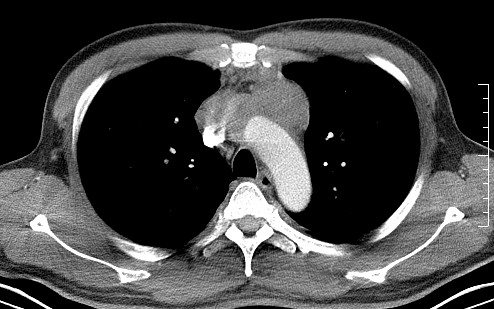

男   40   反复腹痛入院行彩超检查示胸骨右缘4、5肋间不均质回声团

淋巴瘤:前纵隔可见多组肿大的淋巴结,部分融合,有液化坏死